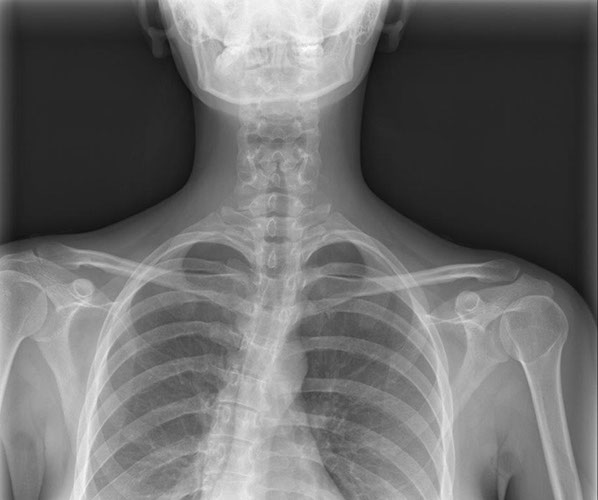

Herz-/Lungenröntgen (Thorax-Röntgen)

Die Untersuchung muss mit tiefer Einatmung (Inspiration) durchgeführt werden. Dies erlaubt eine bessere Beurteilbarkeit der Lunge. Es ist auch wichtig, dass Sie sich während der Aufnahme nicht bewegen. Es werden zwei Aufnahmen im Stehen gemacht. Im Anschluss an das Röntgen wird von der Radiotechnologin die Bildqualität geprüft und erfolgt danach die Befundung durch den Radiologen.